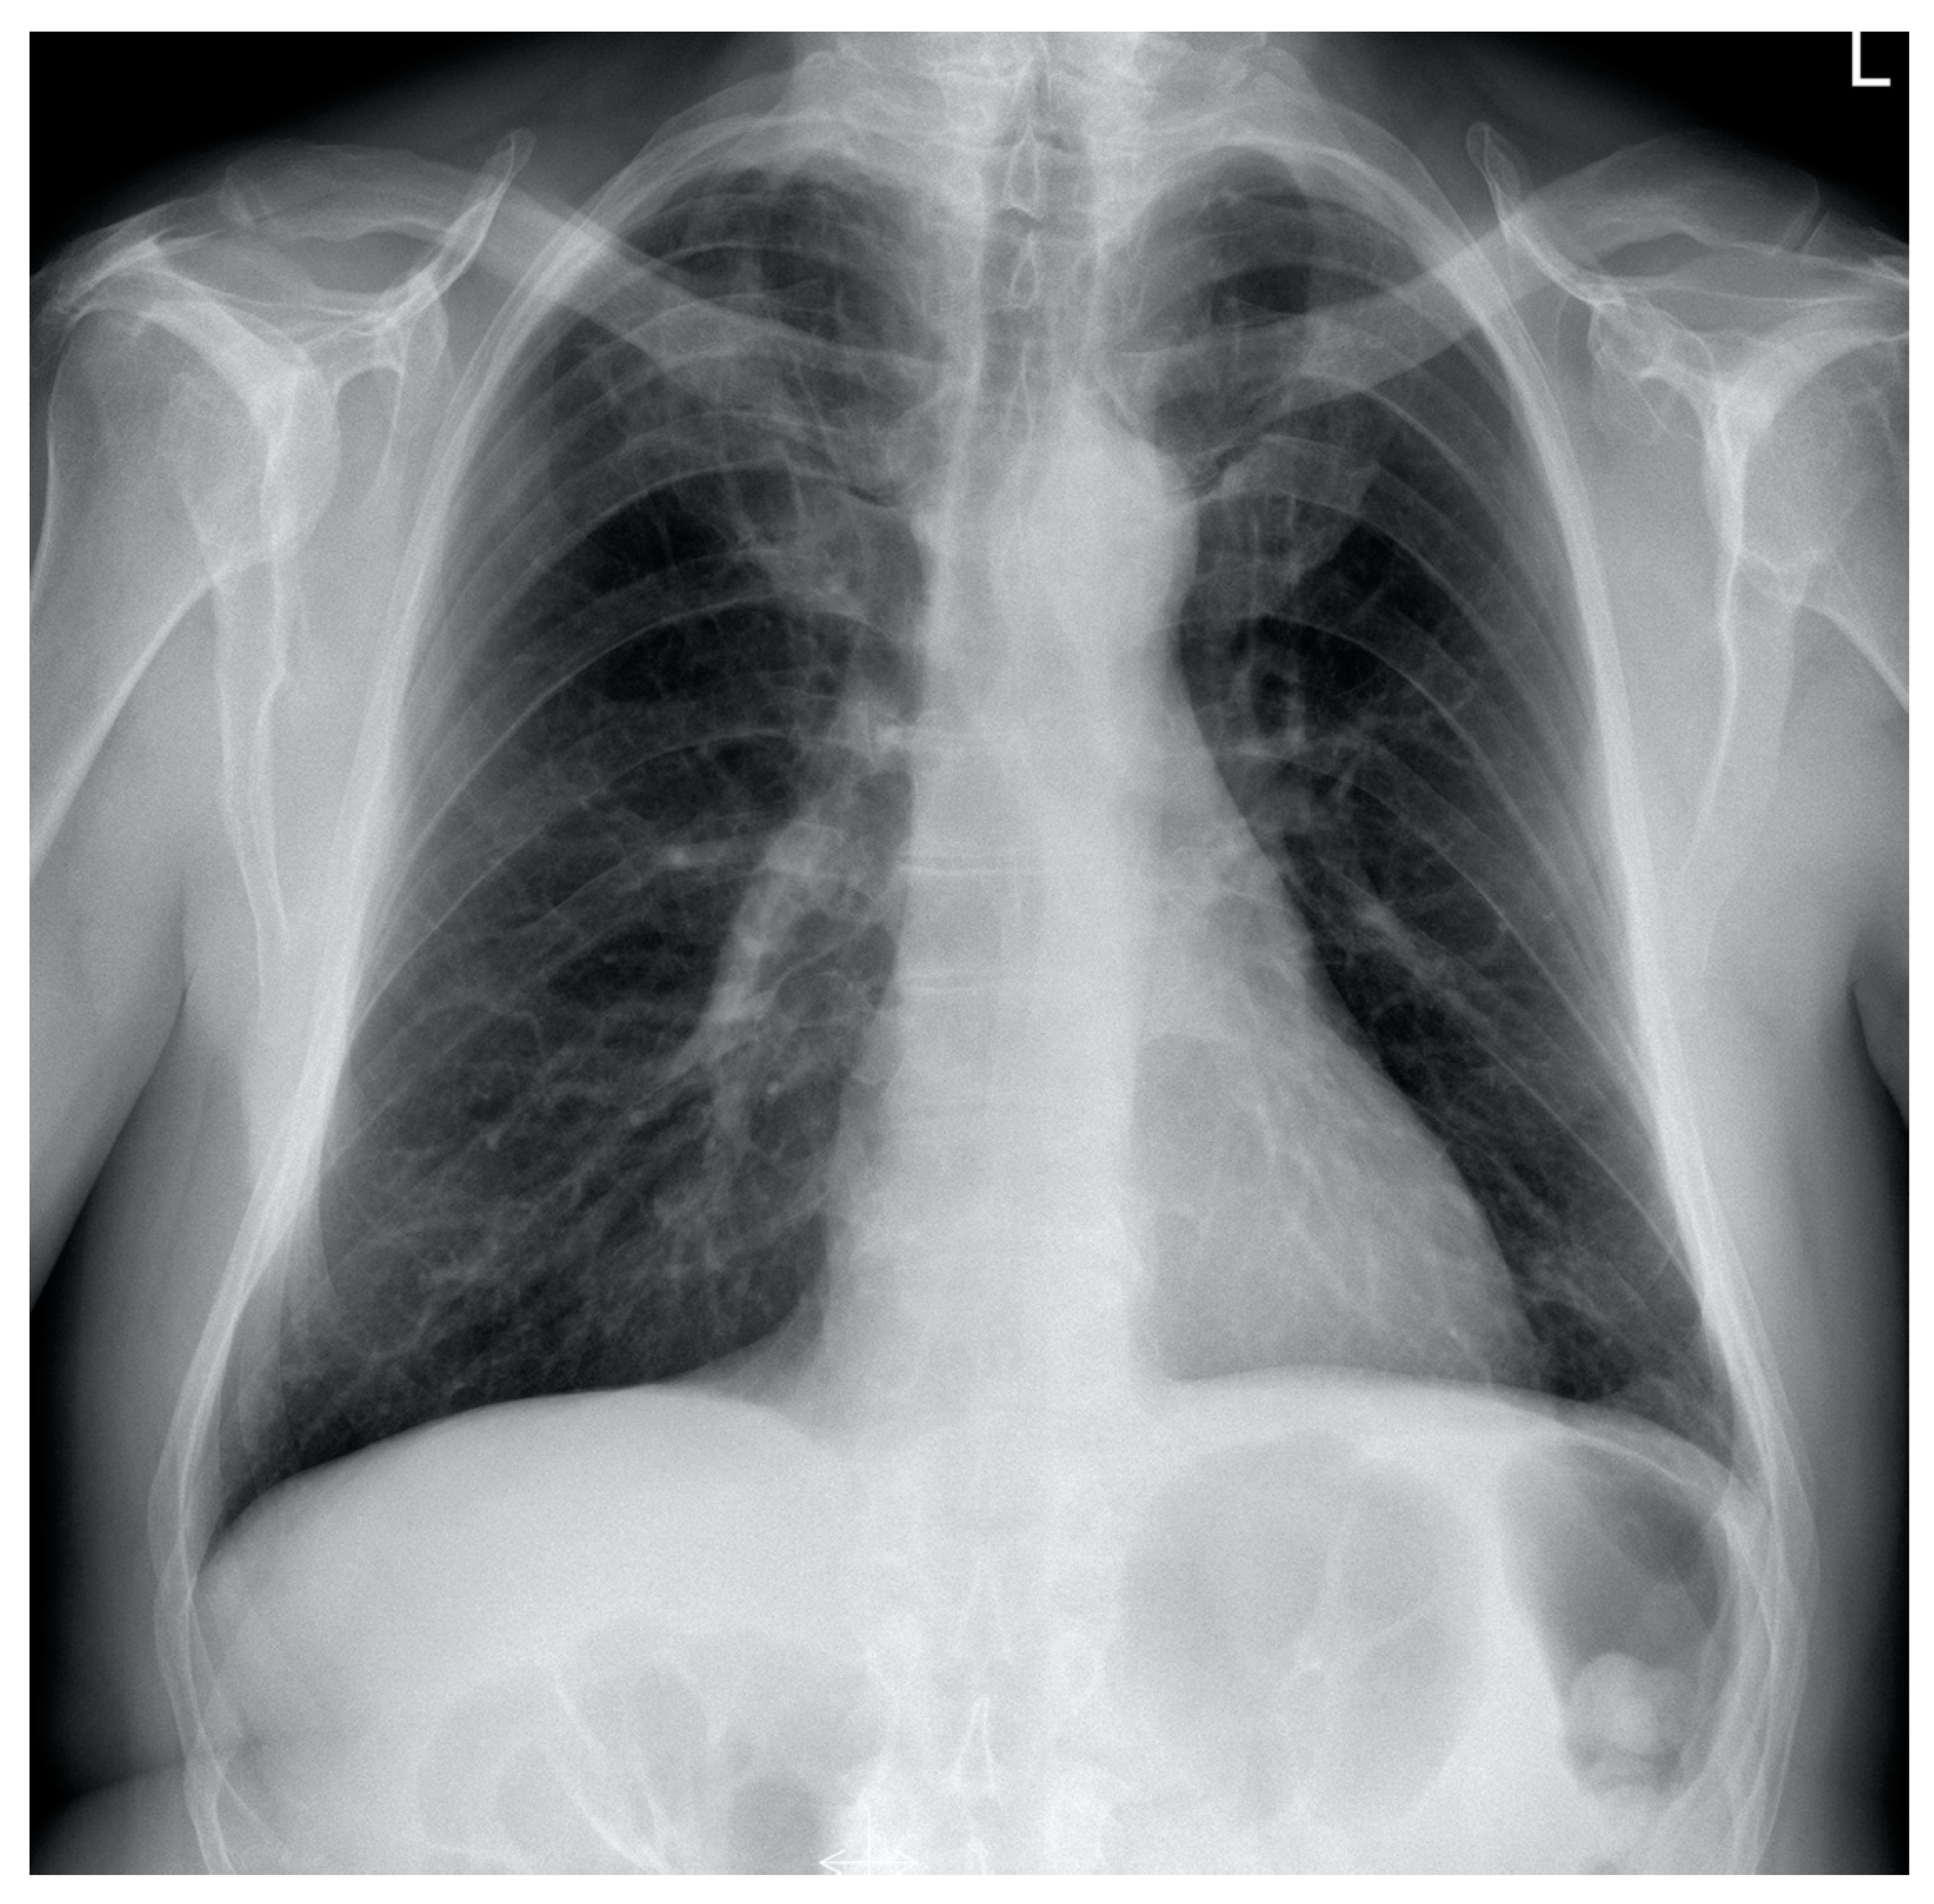

| Radiological picture | Pulmonary embolism, parenchymal infiltrates, bilateral pleural fluid | Regression of PA thrombi, pleural fluid and parenchymal consolidations | Complete resolution of PA thrombi, pleural fluid and lung consolidations | |